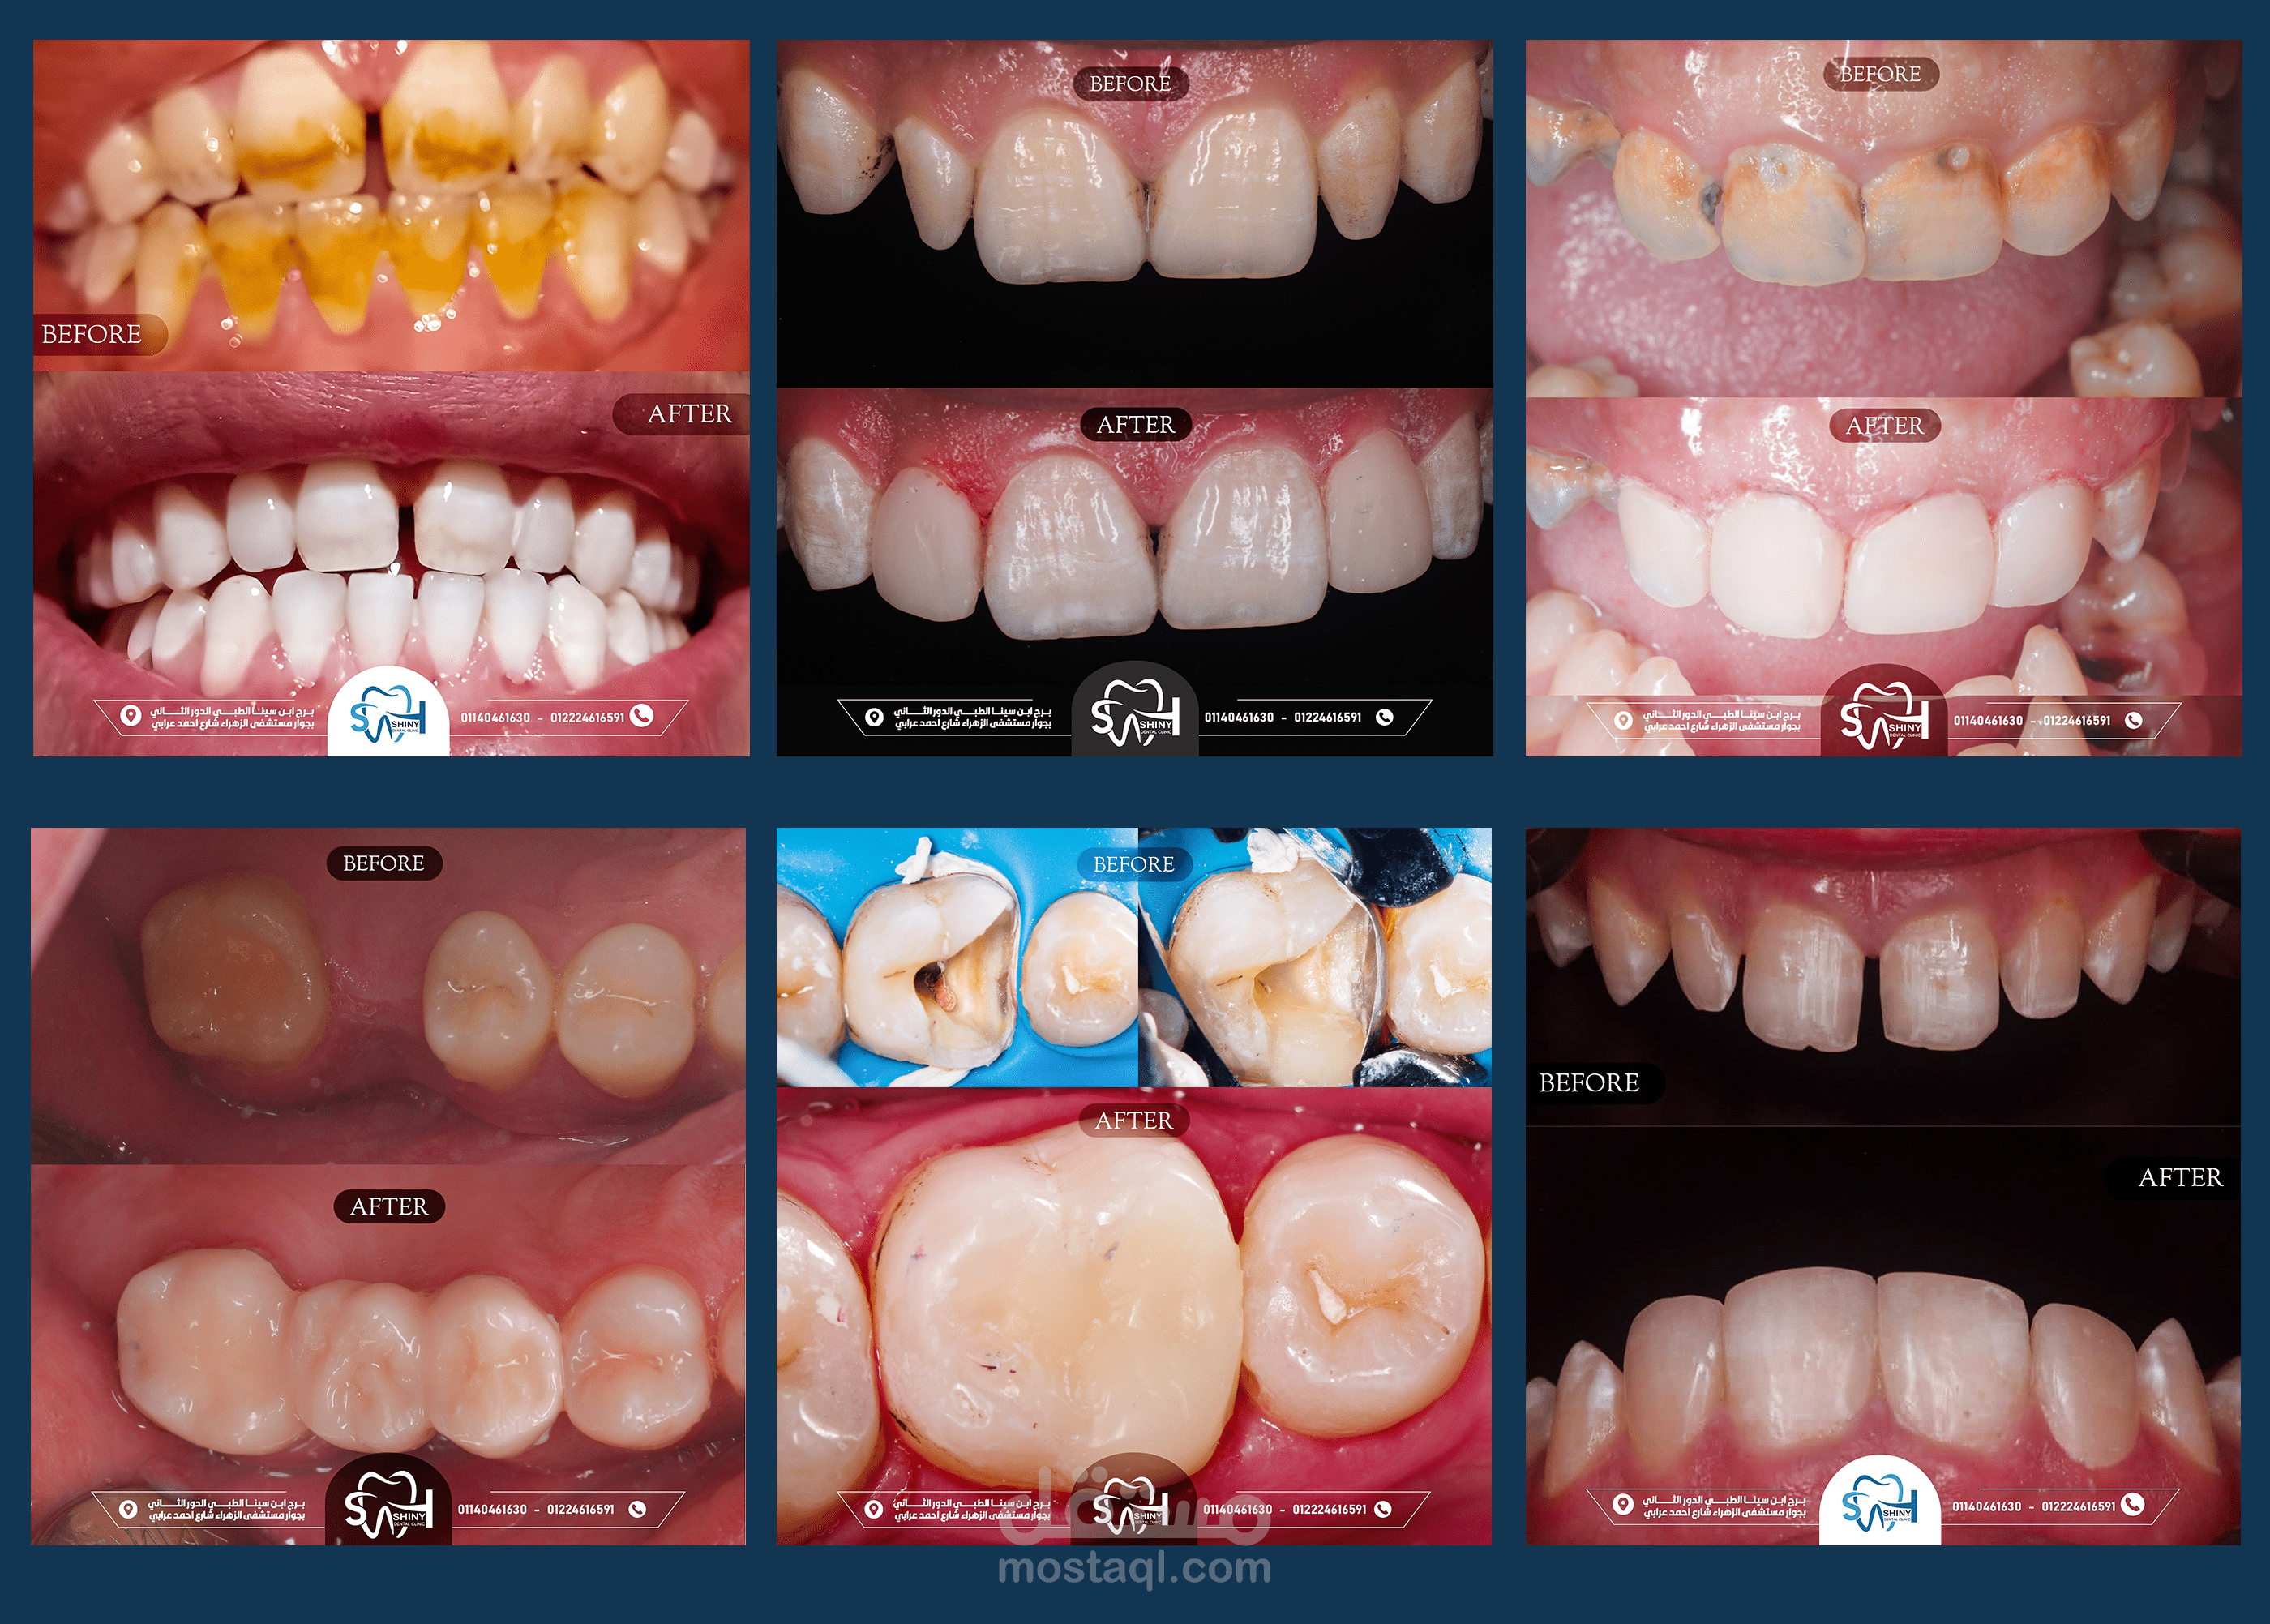

تصاميم سوشيال ميديا لصالح عيادة اسنان- shiny dental clinic.

هذه المجموعة من التصاميم تم إعدادها خصيصًا لعيادة shiny dental clinic, ,وهي تهدف إلى تعزيز الهوية البصرية للعيادة على منصات التواصل الاجتماعي، وزيادة التفاعل مع الجمهور, مع تسليط الضوء على الخدمات المقدمة والعروض الخاصة. تم التركيز في التصاميم على الألوان النظيفة والمريحة التي تعكس طابع العيادة الحديث والاحترافي، مع الحفاظ على أسلوب بسيط وجذاب يواكب تطلعات الجمهور المستهدف.